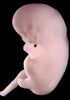

Carnegie Stage 19 (47 post-ovulatory days)

Most embryos at stage 19 are approximately 47-48 post-ovulatory days old and measure 17-20 mm in length. Distinguishing criteria for this stage include straightening of the trunk, the limbs extend nearly directly forward, toe rays are prominent, but interdigital notches have not yet appeared in the foot.

Although some of the photographs below show abnormal embryos, the animations and MRI slice images all depict normal embryos. Abnormal embryos are noted in the titles of the large photos when they are opened.